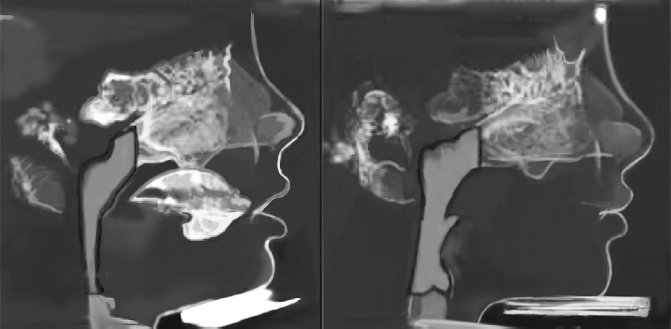

Рисунок 6. Результаты лечения, проведенного ортодонтом Джоном Мью (фотографии любезно предоставлены Джоном Мью)

Рисунок 7. Расширение дыхательных путей у мальчика после ортотропического лечения и исправления осанки лица. Подобный эффект продемонстрирован на шестом рисунке